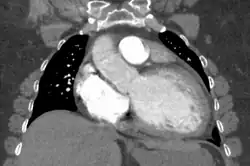

Dilated cardiomyopathy on CT

The electrocardiogram often shows sinus tachycardia or atrial fibrillation, ventricular arrhythmias, left atrial enlargement, and sometimes intraventricular conduction defects and low voltage. When left bundle-branch block (LBBB) is accompanied by right axis deviation (RAD), the rare combination is considered to be highly suggestive of dilated or congestive cardiomyopathy.[29][30] Echocardiogram shows left ventricular dilatation with normal or thinned walls and reduced ejection fraction. Cardiac catheterization and coronary angiography are often performed to exclude ischemic heart disease.[28]